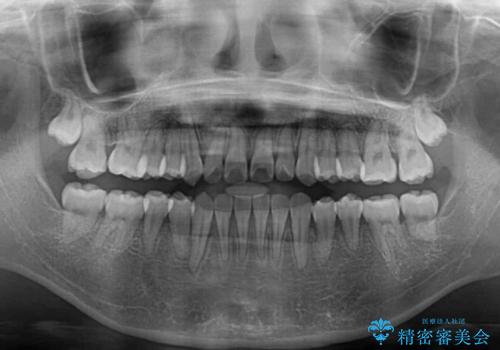

- 前歯の開咬と、上顎前歯の八重歯やデコボコを気にして来院された患者様です。

上顎歯列が狭窄していたため、急速拡大装置により上顎骨を側方に拡大し、その後ワイヤー装置にて矯正治療を行うこととしました。

上顎骨を拡大することで、八重歯やデコボコを歯列に収めることができ、下顎の歯が外に位置していた奥歯の咬み合わせも改善することができました。

スペースも短期間に獲得できるため、1年程度で治療を終えることができました。